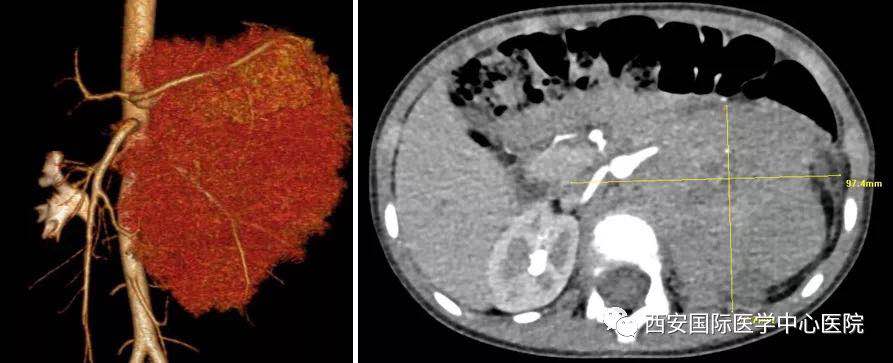

入院后,楊增悅主任仔細詢問病史、查閱影像學資料,第一時間為依依安排骨髓穿刺活檢,最終確診為:腹膜后神經(jīng)母細胞瘤(Ⅳ期/L2)。CT顯示腫瘤巨大,侵及腹主動脈、腹腔干、腸系膜上動脈、雙腎動脈、腸系膜下動脈、下腔靜脈、雙腎靜脈、左腎及腎上腺、胰十二指腸、脾臟、結腸脾曲;腹膜后多發(fā)淋巴結轉移、骨轉移。骨穿病檢示:神經(jīng)母細胞瘤骨髓轉移,腫瘤細胞占90.5%。經(jīng)過科室團隊討論后決定,先行新輔助化療后再進行手術治療。